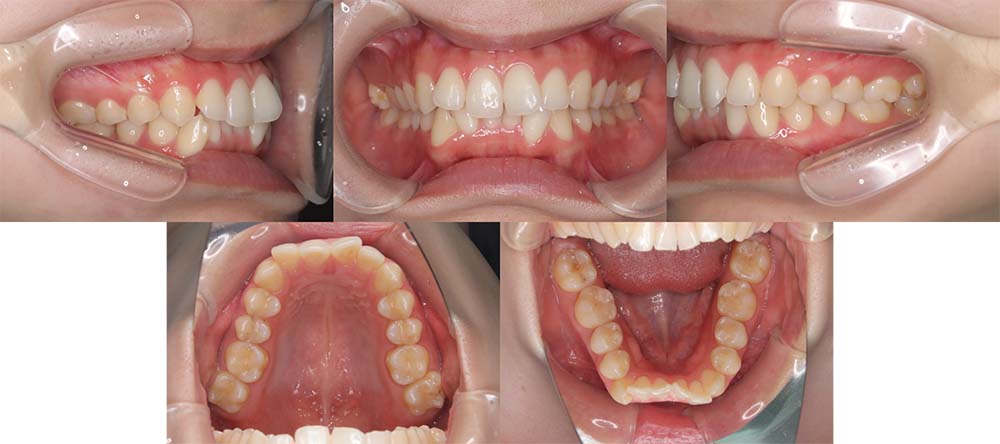

| 症例分類 | 叢生 |

| 診断名 | 上下叢生 |

| 主訴 | 八重歯と下の歯のガタガタが気になる |

| 年齢 | 24歳4ヶ月 |

| 性別 | 女性 |

| 抜歯部位 | 上下左右の第一小臼歯(4本) |

| 使用装置 | 上は裏側、下は表側のワイヤー装置 |

| 治療期間 | 2年8ヶ月 |

| 保定装置 | 固定式保定装置、取り外し式保定装置(8時間) |

| 費用 |

[検査・診断料] ¥49,500 [基本施術料] ¥1,056,000 [調整料] ¥5,500/回 [抜歯] ¥5,500/本 [保定装置] ¥55,000(税込) 抜歯や虫歯治療は他院にて費用が別途かかります。(抜歯¥4,000〜10,000/本)

上下叢生のため、上下第一小臼歯を抜去して上裏側下表側のハーフリンガルで治療しました。

顎間ゴムは治療期間の半年程度使用しましたが、協力度が良好だったためしっかり咬合することができました。

治療開始前にホワイトニングをしたこと、咬合力が強いためか装置の脱離が多く、予定より治療期間が伸びてはしまいました。